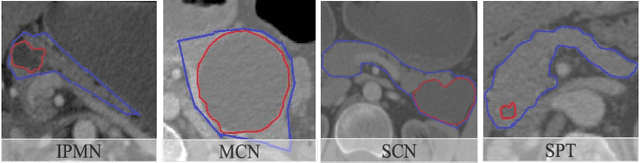

Abstract:The lethal nature of pancreatic ductal adenocarcinoma (PDAC) calls for early differential diagnosis of pancreatic cysts, which are identified in up to 16% of normal subjects, and some of which may develop into PDAC. Previous computer-aided developments have achieved certain accuracy for classification on segmented cystic lesions in CT. However, pancreatic cysts have a large variation in size and shape, and the precise segmentation of them remains rather challenging, which restricts the computer-aided interpretation of CT images acquired for differential diagnosis. We propose a computer-aided framework for early differential diagnosis of pancreatic cysts without pre-segmenting the lesions using densely-connected convolutional networks (Dense-Net). The Dense-Net learns high-level features from whole abnormal pancreas and builds mappings between medical imaging appearance to different pathological types of pancreatic cysts. To enhance the clinical applicability, we integrate saliency maps in the framework to assist the physicians to understand the decision of the deep learning method. The test on a cohort of 206 patients with 4 pathologically confirmed subtypes of pancreatic cysts has achieved an overall accuracy of 72.8%, which is significantly higher than the baseline accuracy of 48.1%, which strongly supports the clinical potential of our developed method.